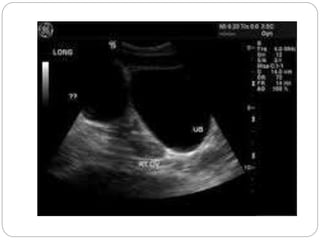

Parapelvic cyst

Severe hydronephrosis with

proximal hydro ureter

Moderate hydronephrosis on

right and severe on left